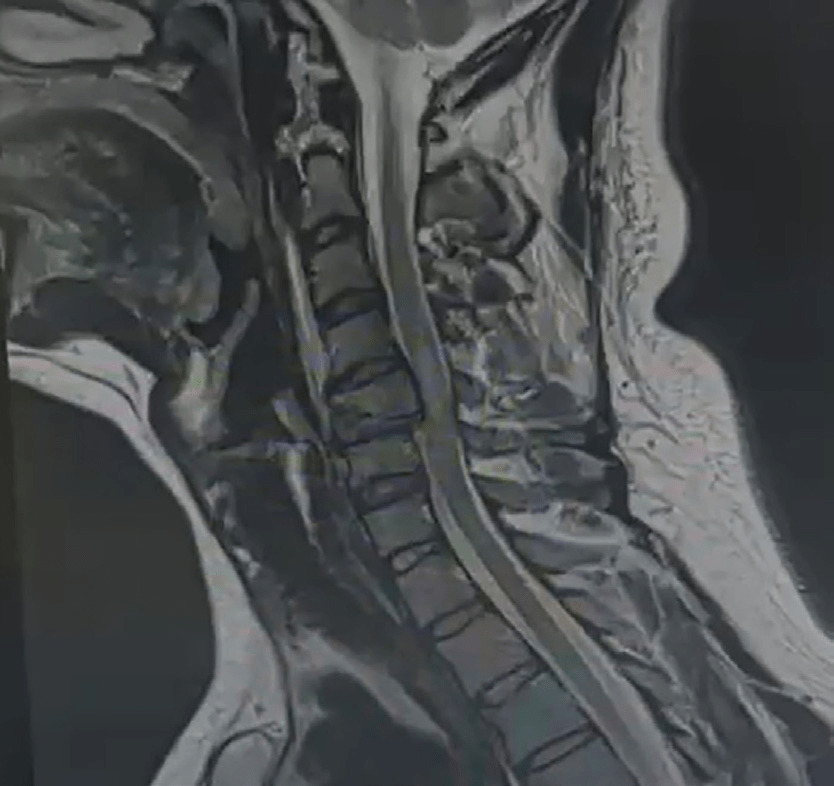

RX lateral de columna cervical (Fig. 1), solución de continuidad en cuerpo vertebral de C5, pérdida parcial de la altura del cuerpo, sin presencia de incongruencia de articulaciones facetarias, pérdida de lordosis cervical. RM simple de columna cervical (Fig. 2), protrusión de disco vertebral C5-C6 y cuerpo vertebral C5 hacia conducto medular.